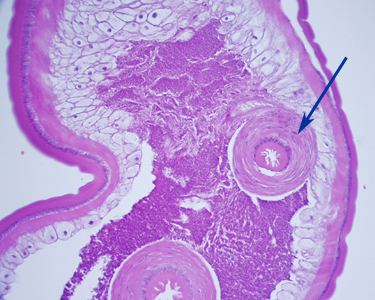

Case #248 – March, 2009

A 36-year-old immigrant from Mozambique presented to his health care provider with heartburn and chronic right abdominal pain. All previous ova and parasite (O&P) examinations were negative. An endoscopy was performed, upon which a worm-like object was observed in the ascending colon near the ileocecum. The suspicious object, measuring approximately 7 mm in length, was removed, collected in 10% formalin, and sent to Pathology for work-up. The object was sectioned, stained with hematoxylin and eosin (H&E) and reviewed by the attending pathologist, who in turn captured the following images and sent them to DPDx for telediagnosis assistance. What is your diagnosis? Based on what criteria?

Figure B